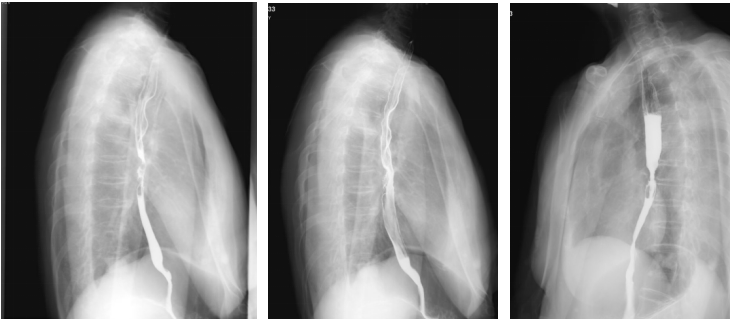

上消化道钡剂造影(2020-08-14):相当于胸7-9椎体水平的食道见范围长约35mm的狭窄段,管壁僵硬,粘膜皱襞破坏、中断,轮廓不光整,可见偏心性充盈缺损及小刺状龛影,狭窄段以上食管轻度扩张,对比剂排空延迟,余食道壁柔软,粘膜规则,未见充盈缺损及龛影,未见异常狭窄及扩张,贲门结构正常,开闭自如。

胸部平扫+增强CT(2020-08-27):食道中段管壁增厚,上下累及约4.5厘米(约胸5/6椎间隙水平至胸8椎体上缘水平),增强后可见轻度强化,隆突下见境界不清淋巴结。左肺上叶尖后段及相邻左肺下叶背段交界处见团块状直径约2.5厘米软组织密度灶,边缘可见毛刺,左侧胸腔积液,左下肺膨胀不全。右肺下叶见少许条状影。结论:1、食管癌。2、左肺上叶尖后段病灶,符合肺癌。左侧胸腔积液,左下肺膨胀不全。